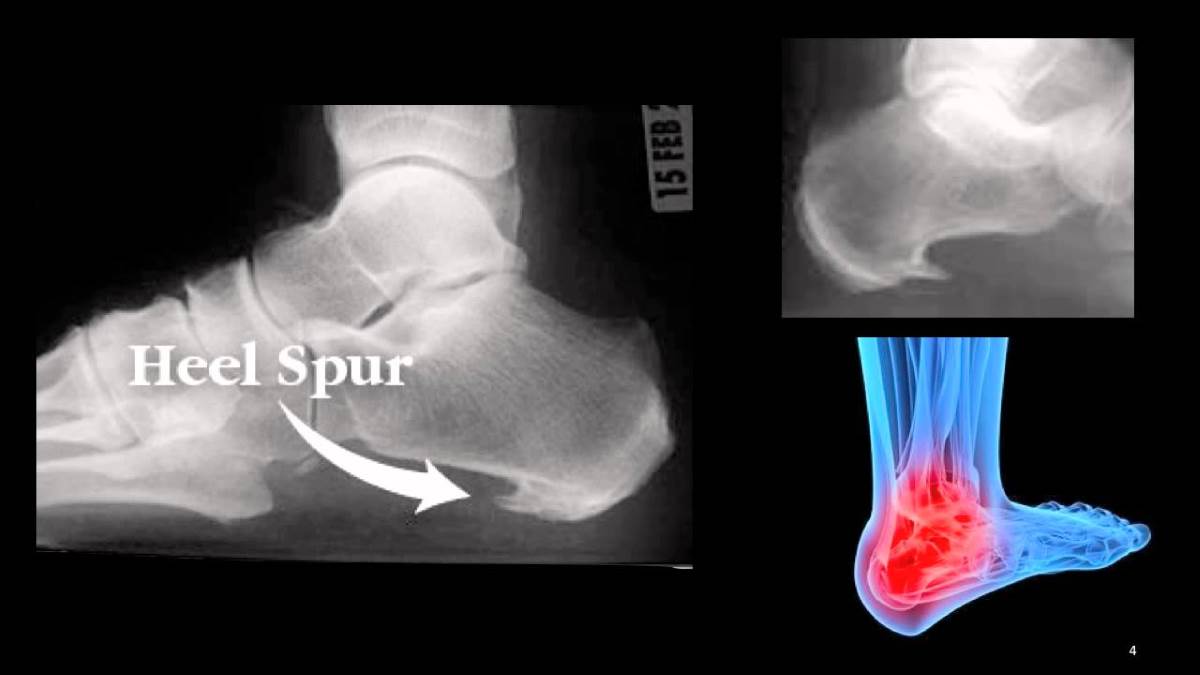

Главная Пяточная шпора Пяточная шпора Что такое пяточная шпора

Что такое пяточная шпора

Полный размер 1200 × 675 пикселей Пяточная шпора